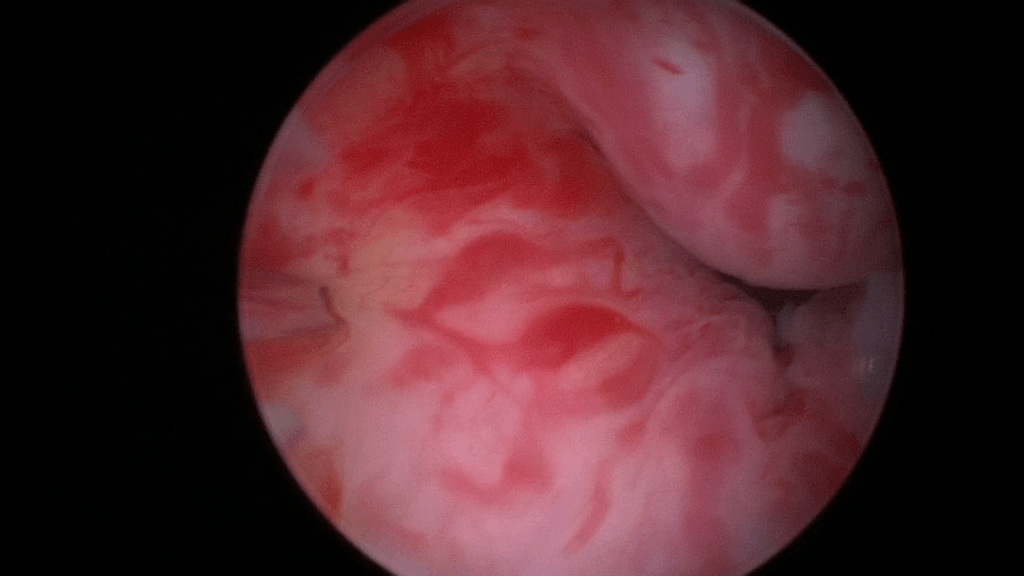

Beginn with a thorough cystoscopy. Patients that have incontinence recurrence should be examined for sling or even suture erosion. Watch out for tumors or stones.

The bladder neck.